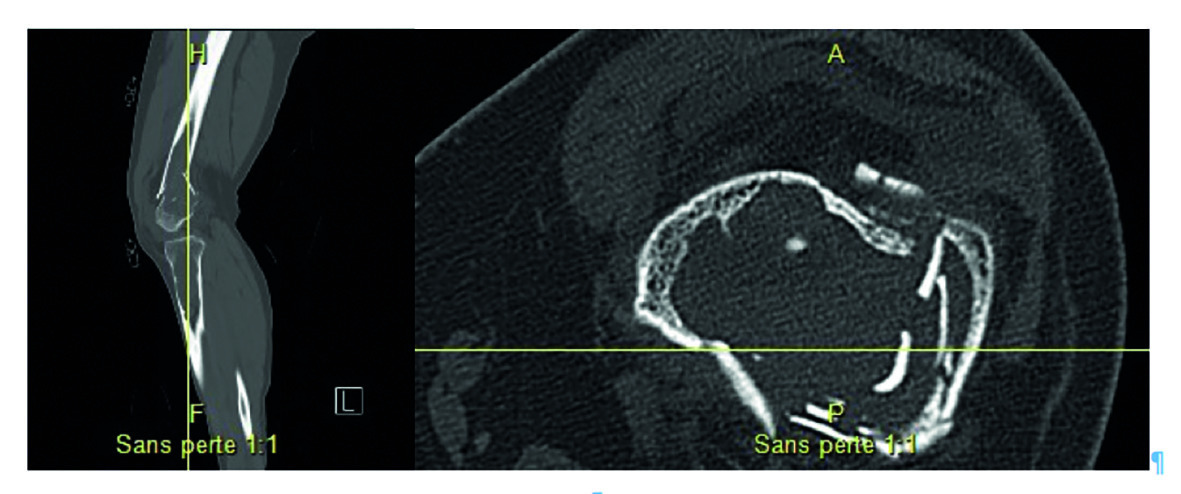

Les radios montrent une fracture fermée comminutive déplacée, supracondylienne, du fémur (fig. 1), dont la sévérité fait suspecter une pathologie sous-jacente. On note plusieurs lésions ovalaires hyperclaires et un amincissement de la corticale osseuse au niveau du tiers distal du fémur et du tibial proximal gauches (fig. 1 ; kystes lacunaires au scanner, fig. 2 ), mais aussi des lésions lacunaires bilatérales diaphysaires et métaphyso-diaphysaires.

Les radios montrent une fracture fermée comminutive déplacée, supracondylienne, du fémur (fig. 1), dont la sévérité fait suspecter une pathologie sous-jacente. On note plusieurs lésions ovalaires hyperclaires et un amincissement de la corticale osseuse au niveau du tiers distal du fémur et du tibial proximal gauches (